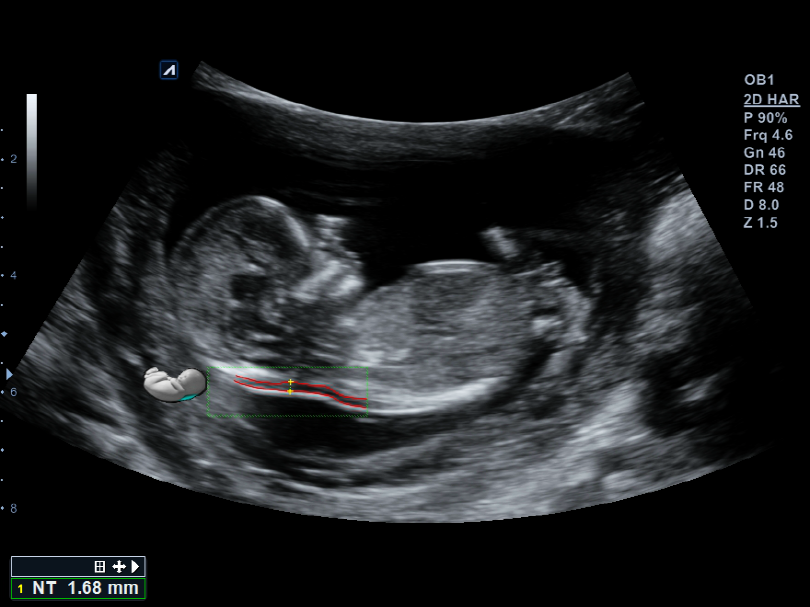

VC1-6T

Volume Convex (1-6MHz)

Application:

Abdomen, OB, GYN, EM

VE3-10H

High density volume endocavity transducer (3-10MHz)

Application:

GYN, OB, Urology, EM